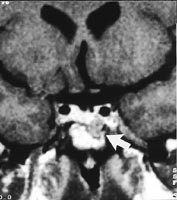

Radiologisk verifisering og kartlegging av tumor skjer fortrinnsvis ved MR-skanning (fig 3). På bakgrunn av sykdommens langsomme utvikling har adenomet ofte en betydelig størrelse og utbredelse ved diagnosetidspunktet, hvilket indirekte sier noe om de somatotrope cellers relativt beskjedne hormonproduksjon. Generelt skiller man mellom svulster som kun har sin utbredelse i sellagropen, såkalte mikroadenomer (<10 mm i diameter), og svulster som i tillegg til intrasellær vekst også vokser ut av sella. Veksten kan skje i ulike retninger – lateralt inn i sinus cavernosus (fig 4), oppover mot de basale cisterner og chiasma og nedover i sinus sphenoidale. De preoperative bilder kan ofte indikere om tumor lar seg radikaloperere, og har derfor stor prognostisk verdi (12, 17, 18).